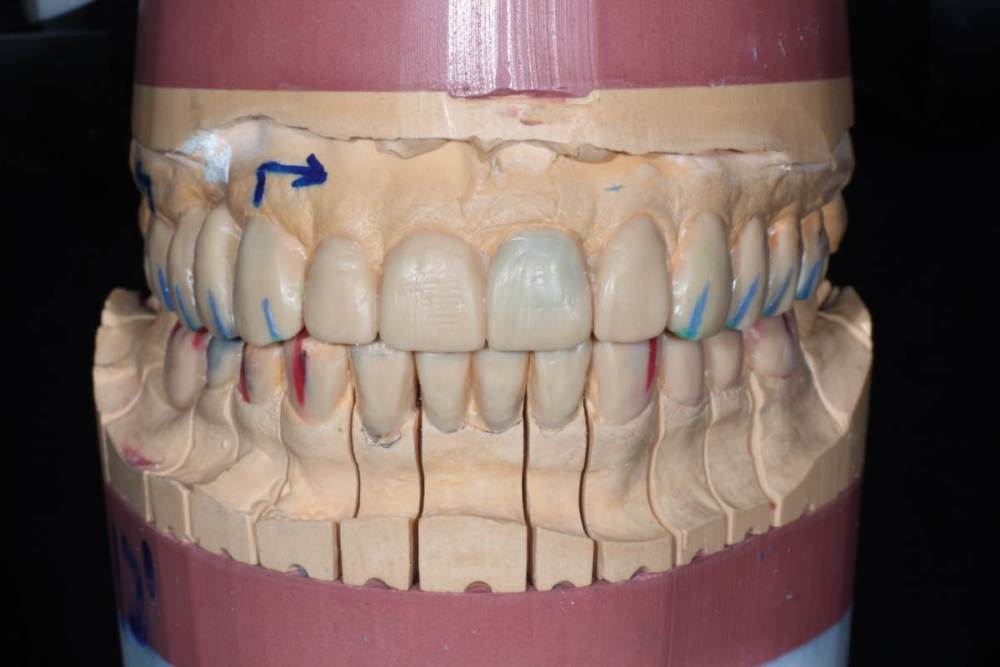

2)Восковое моделирование по Славичеку

Восковое:

IMG_0829.thumb.JPG.608bdcb27c9ca9b2e55fe274d2ecfaf6.JPGIMG_0819.thumb.JPG.d8bb2ec3c123dcd85b14b25693f83c09.JPGIMG_0825.thumb.JPG.6346606830caa517d44fe225ac9d40bf.JPG

Для сравнения ситуация до:

1118463997_ICP(2).thumb.JPG.6ea5ace5a0ac58ccc721805c17d53dc0.JPG